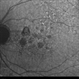

- geographic atrophy

- AMD, geographic atrophy